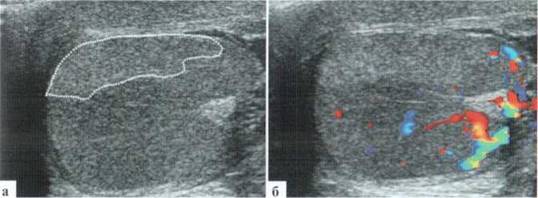

Орхит у детей встречается редко, чаще в подростковом возрасте, но зафиксирован и у новорожденных. Причина заболевания не всегда ясна, клинико-лабораторное подтверждение инфекции мочевыводящих путей, которой отводится известная роль в генезе орхитов и эпидидмитов, имеет место далеко не всегда. Характерны весьма разнообразные изменения структуры яичка в В-режиме: от редко выраженных до практически не дифференцируемых. В большинстве случаев имеет место некоторое увеличение яичка в размерах, преимущественно — в толщину, при этом оно приобретает шаровидную форму. Эхогенность паренхимы может оставаться нормальной, может диффузно понижаться. Всегда имеется значительное усиление сосудистого рисунка в паренхиме яичка. Часто определяется некоторое снижение RI артериального тестикулярного кровотока, но, строго говоря, количественная оценка тестикулярного кровотока при гиперемии яичка у детей с орхитами редко дает принципиально новую информацию для оценки состояния пораженного органа. Часто определяется утолщение оболочек яичка за счет их отека и небольшое количество жидкостного содержимого в оболочках (рис. 2.3.1).

Рис. 2.3.1. Орхит слева у ребенка 11 лет: а, б — правое неизмененное яичко 32x15 мм; в, г — левое яичка увеличено в размерах до 42x26 мм, паренхима гомогенная, без значительных структурных изменений, резко выраженное диффузное усиление сосудистого рисунка

Весьма демонстративным является поперечное сканирование мошонки, когда датчик располагается перпендикулярно ее шву, и в поле сканирования попадают одновременно оба яичка или хотя бы их внутренние фрагменты. Изменение формы яичка и интенсивности интратестикулярного сосудистого рисунка не вызывают сомнения (рис. 2.3.2).

Рис. 2.3.2. Поперечное сканирование по передней поверхности мошонки у ребенка 13 лет с правосторонним орхитом с одновременной визуализацией фрагмента правого (D) и левого (S) яичек

В редких случаях паренхима яичка при орхите имеет «мозаичный», или «географический» вид, когда имеются сливные поля понижения эхогенности. Обычно сосудистый рисунок усилен именно на этих гипоэхогенных участках (рис. 2.3.3)

Рис. 2.3.3. «Мозаичная» структура яичка и неравномерное выраженное усиление ратестикулярного сосудистого рисунка у ребенка 12 лет с орхитом. Зона понижения зхогенности паренхимы яичка показана пунктиром